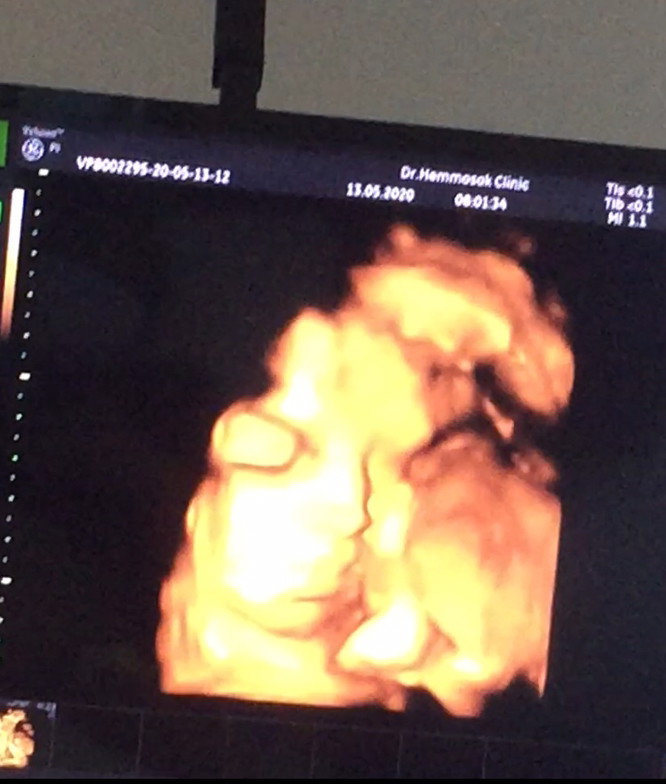

32+5ค่ะ